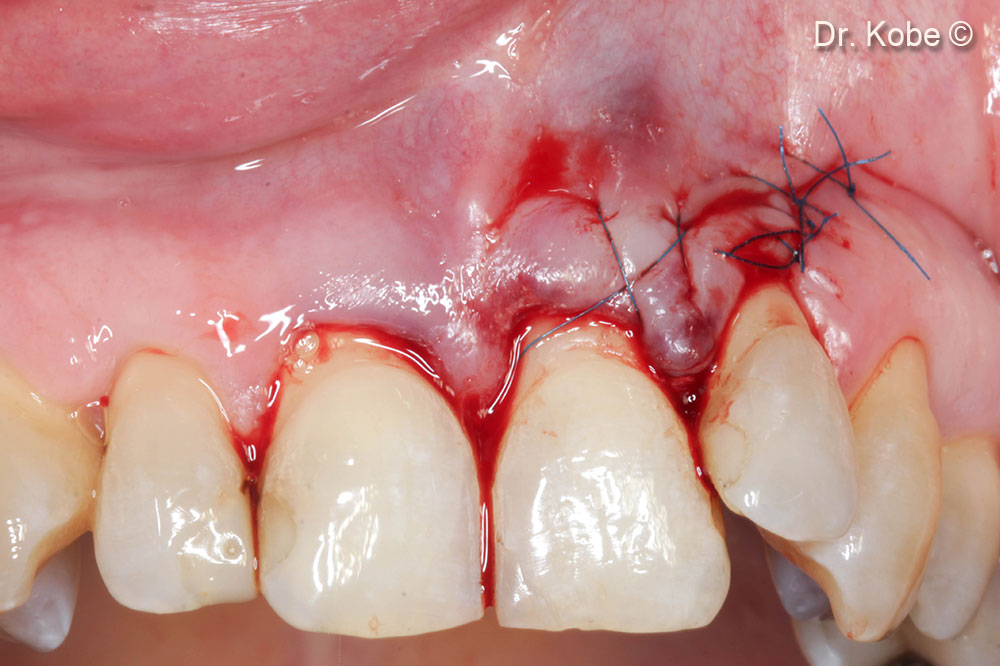

7. Wound sutured with interrupted sutures